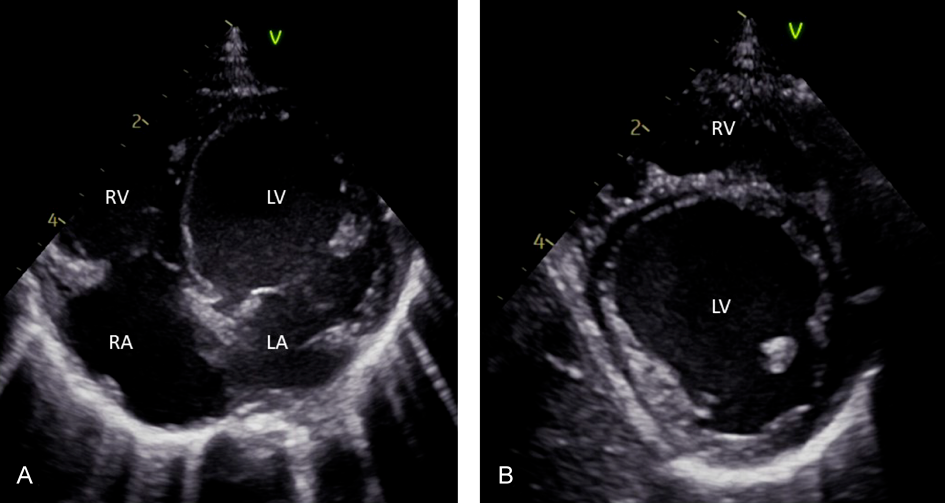

Fig. 1 Transthoracic echocardiography in chronic lymphocytic myocarditis with the phenotype of dilated cardiomyopathy and acute heart failure

A. Transthoracic echocardiography with 4 chamber view in a 1 month old child with myocarditis and phenotype of dilative cardiomyopathy (Left ventricular (LV) ejection fraction 38%, LV diameter 26 mm (Z-Score +3,5); B. short axis view. The endomyocardial biopsy revealed a virus negative chronic lymphocytic myocarditis. Genetic panel diagnostic reveals no pathological result, but WES was currently not performed. LA, left atrium; LV, left ventricular; RA, right atrium; RV, right ventricular